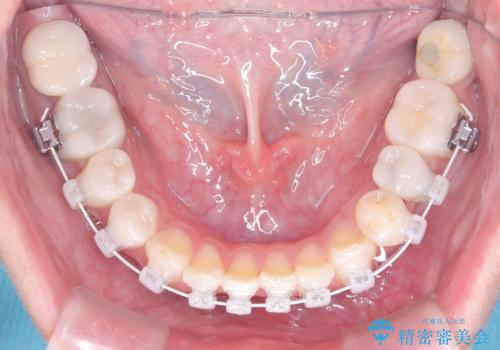

- 40代の患者様で、左上の**八重歯(犬歯の突出)**をずっと気にされていたものの、年齢的な不安から治療を迷われていたとのことでした。精密な検査の結果、左上の歯列に八重歯を収めるための十分なスペースがないことが判明。

40代は歯周組織の健康維持も重要なため、無理な拡大を避け、左上4番(第一小臼歯)を抜歯して確実にスペースを確保する計画を立てました。装置には、歯を三次元的にしっかりとコントロールでき、確実な移動が見込めるワイヤー矯正を選択。八重歯を正しい位置へ誘導し、健康的で美しい口元を目指しました。

まず、計画通り左上4番を抜歯し、そのスペースを利用して八重歯を徐々に正しい位置へと移動させました。ワイヤー矯正特有の「歯を細かく、確実に動かす力」を最大限に活用し、歯根の向きまで丁寧に調整。